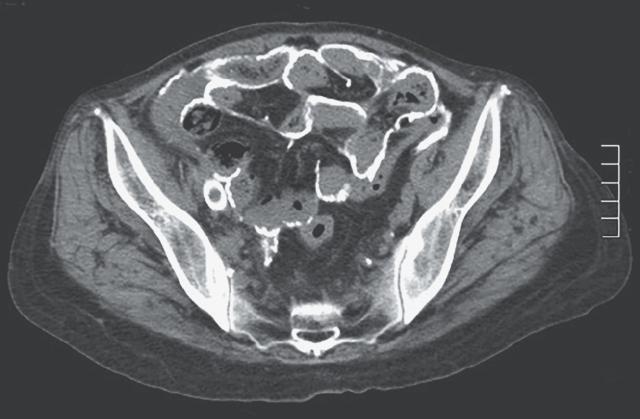

Перитонит кт

Перитонит кт 106 фото